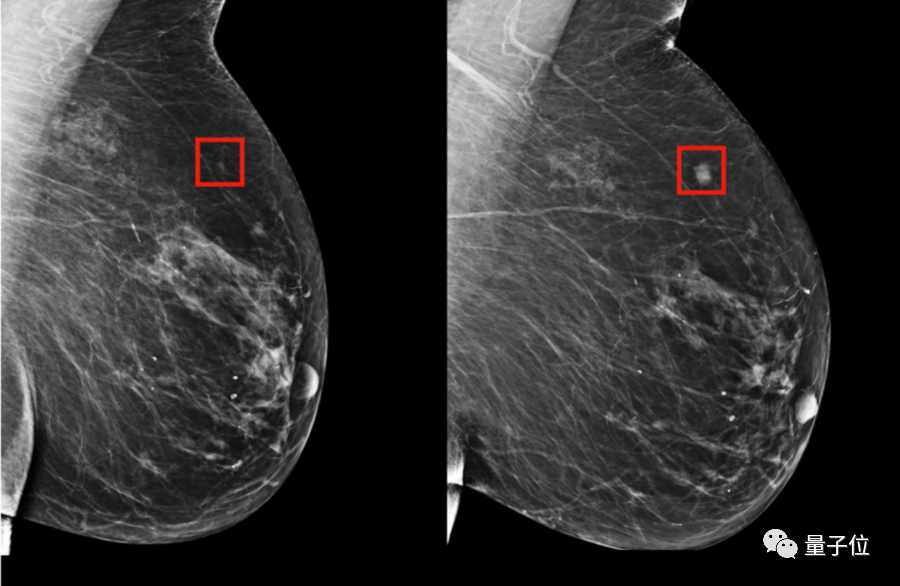

第二个是仅基于X光片图像的深度学习模型;用PyTorch构建了一个深度卷积神经网络ResNet。给定一个乳房的1664 X 2048像素图片,模型会预测是否会在5年内发展成乳腺癌。

在临床对比中,在已确诊的乳腺癌患者中,混合模型在前期就对其中的31%作出了预警,而传统的TC模型的有效预警仅有18%。

目前这项技术已经在新加坡、中国台湾、美国、瑞典等等多家医院进行了测试。